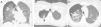

We report the case of a 41-year-old woman with a history of kidney transplantation with chronic graft dysfunction, who was undergoing hemodialysis 3-times-weekly via temporary jugular catheter. The patient was admitted with a diagnosis of catheter sepsis with positive blood cultures for methicillin-resistant Staphylococcus aureus. She developed sudden dyspnea and chest pain 72h after admission. A chest computed tomography was performed that showed right pneumothorax associated with cavitary pulmonary nodules (Fig. 1), some of which were peripheral. A diagnosis of spontaneous pneumothorax following rupture of septic cavitary emboli in the pleural space was established. The pneumothorax was treated with pleural drainage for 4 days. A 4-week course of antibiotic therapy with vancomycin was indicated, with good clinical progress.

Catheter-associated infection is a frequent cause of septic pulmonary embolism.1 The causative microorganism is usually Staphylococcus aureus. Lesions are cavitary in 56% of cases1 and, when they occur in a peripheral site, they can open to the pleural space, triggering secondary spontaneous pneumothorax.2 This complication is rare and usually occurs between 5 and 15 days after starting antibiotic treatment.2